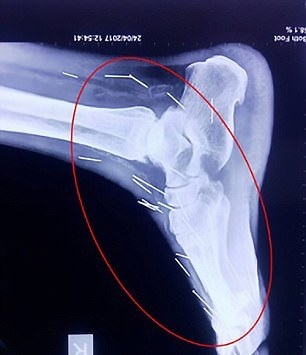

این مرد که «بادریلال مینا» نام دارد و در ایالت راجستان زندگی می‌کند برای عمل جراحی روی انگشت پایش به بیمارستان مراجعه کرد و پزشکان دریافتند سوزن های زیادی در پای او وجود دارد. بررسی‌های بیشتر نشان داد سوزن های دیگری نیز در بدن این مرد 56 ساله وجود دارد.

تاکنون هیچکدام از بیمارستان‌هایی که این خانواده به آنها مراجعه کرده‌اند حاضر نشده‌اند برای خارج کردن این سوزن‌ها از بدن او کاری انجام دهند. از این 70 سوزن، 40 عدد از آنها در گلو، 25 عدد در پای راست و 2 عدد نیز در دو دست او است.